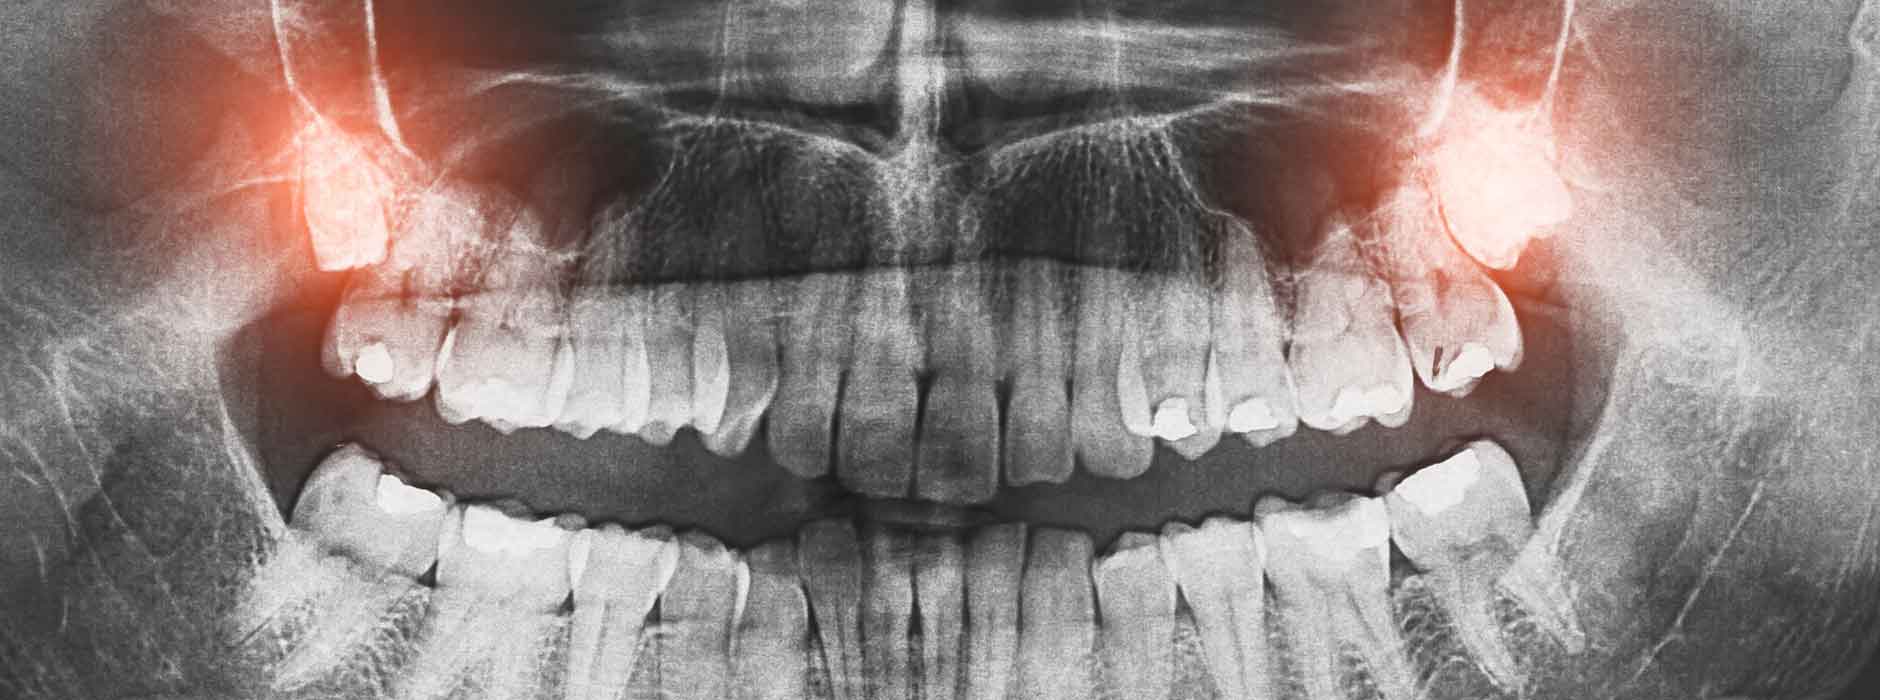

Haben sie krankhafte Veränderungen an Kiefer und Zähnen verursacht? Oder sind solche Veränderungen zu erwarten? Wie hoch ist das Risiko einer Entfernung? Erst, wenn diese Fragen geklärt sind, sollten Arzt und Patient eine Entscheidung fällen. Röntgenbilder geben dabei genaue Auskunft über den Zustand und die Stellung eines Weisheitszahns und seinen Wurzeln. Um festzustellen, ob eine Operation notwendig ist, sind manchmal mehrere Röntgenbilder erforderlich. Das Wachstum der Weisheitszähne muss über einen längeren Zeitraum protokolliert und kontrolliert werden.

Das geschieht mit dem sogenannten Orthopantomogramm, einer zweidimensionalen Röntgenaufnahme von Ober- und Unterkiefer. Hier erkennt der Zahnarzt, ob sich die Weisheitszähne normal entwickeln werden. Er kann auch feststellen, ob bereits krankhafte Veränderungen am Zahn selbst oder an seiner Umgebung vorliegen.